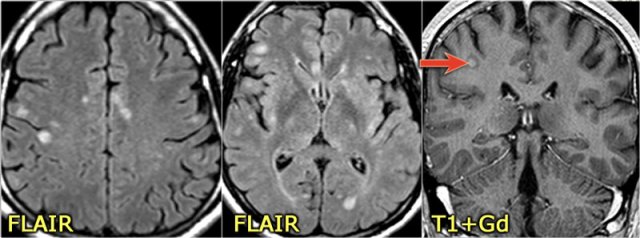

Brain lesions in NMO

Previously it was thought that in NMO the brain was spared, but now we know, that brain lesions do occur.

They are often distinct from those seen in MS.

In Asia 60-80% of patients with NMO have brain abnormalities.

In Europe only 25-40%.

The location of the brain lesions in NMO is only around the ventricles.

The reason why these brain lesions are located around the ventricles is the following:

The NMO IgG auto-antibodies are directed against Aquaporin-4 water-channels.

So just like sodium- and potassium channels in the cells, there are also water-channels.

The highest concentration of these Aquaporin-4 water-channels is seen around the ventricles.

The images show abnormal signal around the third and frontal horns of the lateral ventricles.